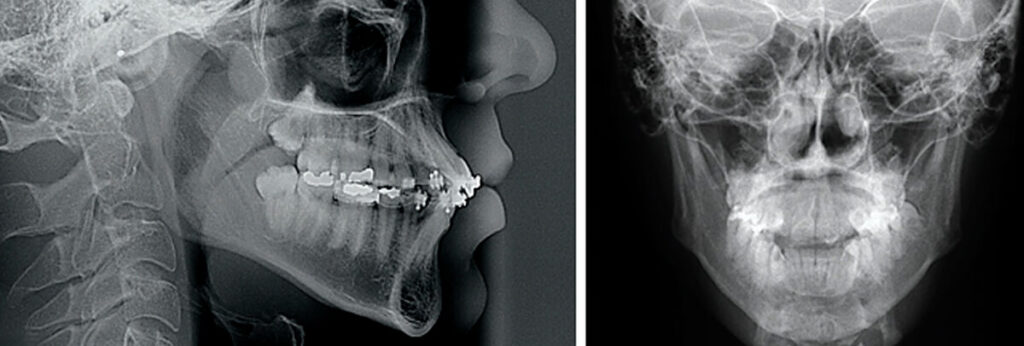

Filme Radiográfico Cefalométrico

O cefalométrico é essencial em ortodontia e na cirurgia ortognática, pois permite mensurações cefalométricas precisas para diagnóstico e planejamento.

Com ele, o ortodontista consegue avaliar a relação entre estruturas craniofaciais, arcadas dentárias e base do crânio.